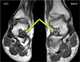

Flat feet (also called pes planus or fallen arches) is a postural deformity in which the arches of the foot collapse, with the entire sole of the foot coming into complete or near-complete contact with the ground. There is a functional relationship between the structure of the arch of the foot and the biomechanics of the lower leg. [Source: Wikipedia ]